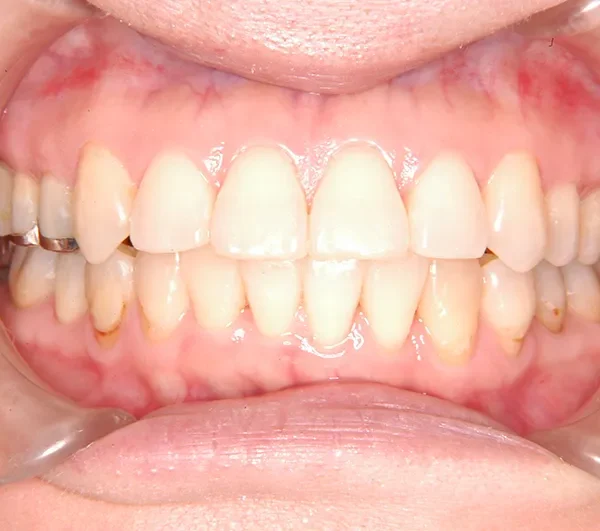

治療終了後

治療回数35回、2年8ヶ月の治療期間で矯正治療を終了しました。

噛み合わせが安定する事で、大きくなっていた咬筋が正常な大きさになり、顎のラインもシャープになり大変よろこばれていました。